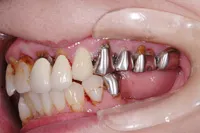

咀嚼障害のため来院されたケース(all-on-4)

60代 男性

咀嚼障害、歯茎の痛みを訴えられ、来院されました。

■治療前

■治療後

| 主訴 | かみにくい・全体的に歯茎が腫れて痛みがある 痛みがある |

|---|---|

| 治療方法 | 上下顎に複数本のインプラントを使用し、一体型の補綴物をセット |

| 治療期間 | 約1年 |

| 通院回数等 | 約20回 |

| 費用 | 約600万円 |

| リスク・副作用 | 補綴物が過度な力で破損するリスクがある |